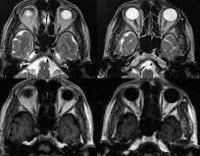

CT orbits.

КТ-орбиты назначают для выявления доброкачественных и злокачественных опухолей, в частности - гемангиом глаза, ретинобластомы. Часто причиной нарушения зрения являются отдаленные метастазы на орбите, распространяющиеся от других органов, пораженных раком. Компьютерная томография орбит показана с механическим повреждением глаз. Сканирование позволяет определить целостность каких структур нарушается, а также установить наличие инородных тел в глазу. В качестве дополнительного диагностического метода его применяют при таких состояниях, как шип, атрофия глазного яблока.

КТ орбиты также используются для выявления воспалительных процессов. Сканирование проводится при подозрении на псевдоопухоль орбиты, при наличии экзофтальма - выпячивание глазного яблока. Показан при гнойных процессах в глазнице - целлюлите, субпериостальном абсцессе. С помощью томографических исследований можно определить степень распространения патологического очага и определить стратегию последующего лечения. Также показанием для КТ-орбит является наличие сильных болей в глазах, быстрое снижение остроты зрения.

По результатам сканирования можно констатировать, что у пациента онкологическое заболевание, определяется тип опухоли, ее точное местоположение и степень распространения на окружающие структуры, а также прогнозируется динамика развития, определяется тактика лечения. Благодаря обнаружению КТ экзофтальма, орбита может определить этиологию заболевания.

КТ-орбита эффективна при диагностике воспалительных и гнойных процессов. На основании полученных данных можно определить частоту поражения близлежащих анатомических структур, чтобы составить план лечения. В случае инородных тел врач может оценить степень повреждения тканей, сделать вывод о необходимости хирургического вмешательства. Контрастный тест позволяет определить уровень кровоснабжения зрительного нерва и глазного яблока. Пациент должен связаться с лечащим врачом, чтобы получить результаты КТ, который поставит точный диагноз и определит следующую стратегию лечения.